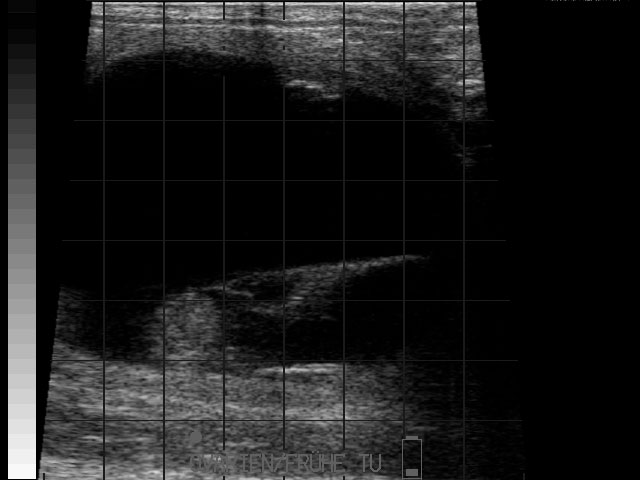

Eierstockstumor

Frühe Resorption